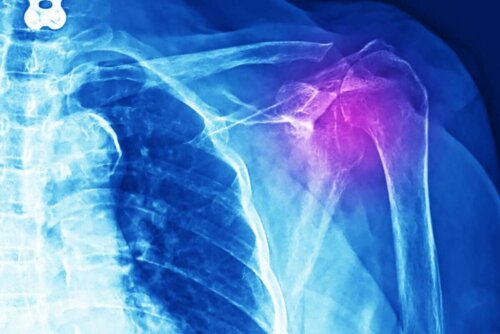

Doctors must do various tests in order to diagnose this kind of injury. It could be an X-ray, an ultrasound, an MRI, or a computerized axial tomography (CT scan). In addition, they must do a medical examination and a detailed study of the patient’s medical history.